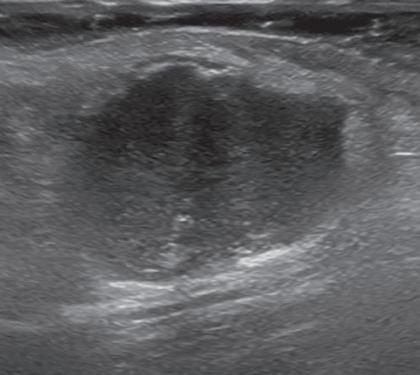

Musculoskeletal structures have characteristic appearances on ultrasound imaging.2 Normal tendons appear hyperechoic with a fiber-like or fibrillar echotexture (see Fig. 1.4).3 At close inspection, the linear fibrillar echoes within a tendon represent the endotendineum septa, which contain connective tissue, elastic fibers, nerve endings, blood, and lymph vessels.3 Continuous tendon fibers are best appreciated when they are imaged long axis to the tendon. On such a long axis image, by convention the proximal aspect is on the left side of the image, with the distal aspect on the right. In short axis, normal hyperechoic tendon fibers appear as bristles of a brush seen on end (see Fig. 1.9A). Normal muscle tissue appears relatively hypoechoic (Fig. 1.6). At closer inspection, the hypoechoic muscle tissue is separated by fine hyperechoic fibroadipose septa or perimysium, which surrounds the hypoechoic muscle bundles. The surface of bone or calcification is typically very hyperechoic, with posterior acoustic shadowing and possibly posterior reverberation if the surface of the bone is smooth and flat (Fig. 1.6). The hyaline cartilage covering the articular surface of bone is hypoechoic and uniform (Fig. 1.7A and B), whereas the fibrocartilage, such as the

labrum of the hip and shoulder, and the knee menisci are hyperechoic (Fig. 1.7B). Ligaments have a hyperechoic, striated appearance that is more compact compared with tendons (Fig. 1.8). In addition, ligaments are also identified in that they connect two osseous structures. Often normal ligaments may appear relatively hypoechoic when surrounded by hyperechoic subcutaneous fat; however, a compact linear hyperechoic ligament can be appreciated when imaged in long axis perpendicular to the ultrasound beam. Normal peripheral nerves have a fascicular appearance in which the individual nerve fascicles are hypoechoic, surrounded by hyperechoic connective tissue epineurium (Fig. 1.9).4 Hyperechoic fat is typically seen around larger peripheral nerves.

FIGURE 1.7 Cartilage. A, Ultrasound image transverse over the distal anterior femur shows hypoechoic hyaline cartilage (arrowheads) F, Femur. B, Ultrasound image of infraspinatus in long axis (I) shows a hyperechoic fibrocartilage glenoid labrum (arrowheads) and hypoechoic hyaline cartilage (curved arrow). Note hyperechoic epidermis and dermis (E/D), and adjacent deeper hypoechoic hypodermis with hyperechoic septa. G, Glenoid; H, humerus.